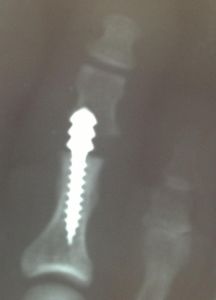

I agree with the simplicity of a K-wire, peg-in-hole, or even splinting the toe with Coban. This patient came in for a second opinion on a painful, swollen toe following a digital implant done a few months ago.

Digital Implant Issue |

To me, it looks like the other doctor missed the middle phalanx - post-op and intra-op films are nowhere to be found. I have some happy patients from taking these out and just removing a little extra bone from the proximal phalanx.